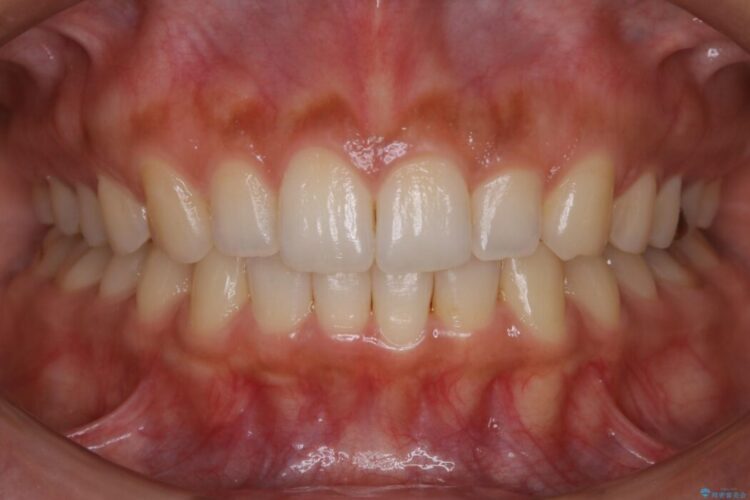

【30代女性】ガタつきのある狭窄歯列を改善する

下顎前歯のガタつきを気にされて来院されました。

叢生の度合いにより抜歯は不要と判断しましたので、歯列幅の拡大を主軸に置き矯正治療を行いました。

本症例では下顎の歯列が舌側へ傾くことにより幅が狭まっていましたので、マウスピース治療により歯列弓を拡大しました。